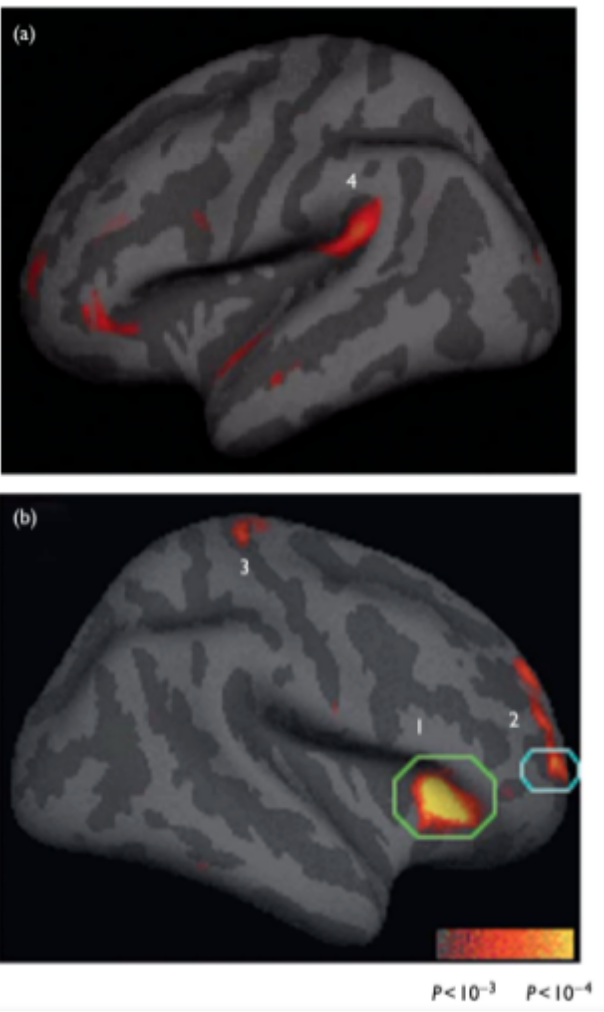

研究发现,和对照组相比,正念训练参与者与注意力、内感和感觉处理相关的大脑区域比对照组更厚,包括前额皮质和右前脑岛等脑区。

(正念冥想者的四个大脑皮质区域明显厚于对照组(a.b)。它们分别是(1)岛叶,(2)右侧额叶(布罗德曼(BA)9/10),(3)体感皮层,(4)听觉皮层。)

作者认为,正念训练是大脑可塑性的训练,可以改变大脑结构。有规律的正念练习与与躯体感觉、听觉、视觉和感觉加工相关的大脑皮层区域的厚度增加存在相关性。